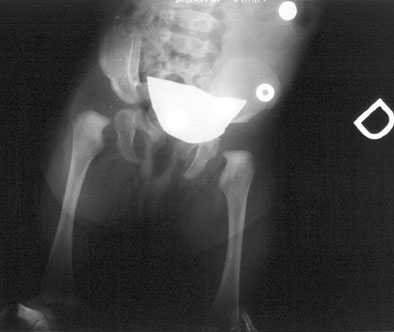

Il trattamento viene iniziato subito e consiste in una riduzione in narcosi con applicazione di un apparecchio gessato pelvi-podalico in I posizione da tenere per 35 giorni. Al primo gesso ne ha fatto seguito un secondo per altri 30 giorni.